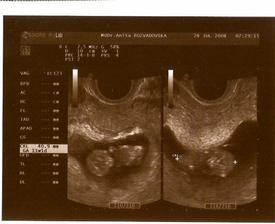

13.června jsem na testu našla // .Hodnota hcg byla 1 307,podle internetu jsem tušila,že to budou dvojčata.Těhotenství bylo téměř ukázkové,i moje dr.říkala,že trháme všechny rekordy,akorát jsem měla těh.cukrovku.30.1.mě poslala do nemocnice,že mi porod 2.2.vyvolají,to ani nebylo třeba,den předtím v 00:30 mi odtekla plodová voda a v 17:43 se narrodila Terezka 49cm a 3,1kg a 17:47 Tomášek 51 cm a 3,2kg spontánně,nakonec i bez epidurálu.Akorát mě nenastřihli,tak mě Terezka natrhla tak 5 cm doprava,ztratila jsem hodně krve,tak jsem byla na infúzích a ještě uvnitř zůstal kousek placenty,tak jsem musela pod narkózu,ale teď už jsem doma a miminka se mají k světu!Já jsem během těhu nabrala 17 kg a teď už mám 19kg dole🙂Jinak děti rostou jak z vody,jsou velcí jedlíci,hlavně Terezka🙂